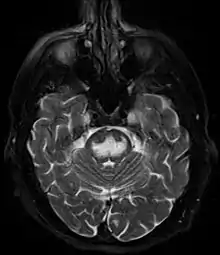

Axial fat-saturated T2-weighted image showing hyperintensity in the pons with sparing of the peripheral fibers, the patient was an alcoholic admitted with a serum Na of 101 treated with hypertonic saline, he was left with quadriparesis, dysarthria, and altered mental status

It can be diagnosed clinically in the appropriate context, but may be difficult to confirm radiologically using conventional imaging techniques. Changes are more prominent on MRI than on CT, but often take days or weeks after acute symptom onset to develop. Imaging by MRI typically demonstrates areas of hyperintensity on T2-weighted images.[29]